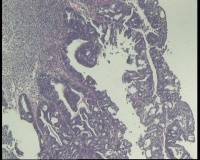

镜下见子宫内膜腺体异型增生,呈乳头状,筛网状排列,细胞核圆形,大小尚均匀,可见少量核分裂像,部分区域鳞化,间质少,部分区域无间质,间质有坏死